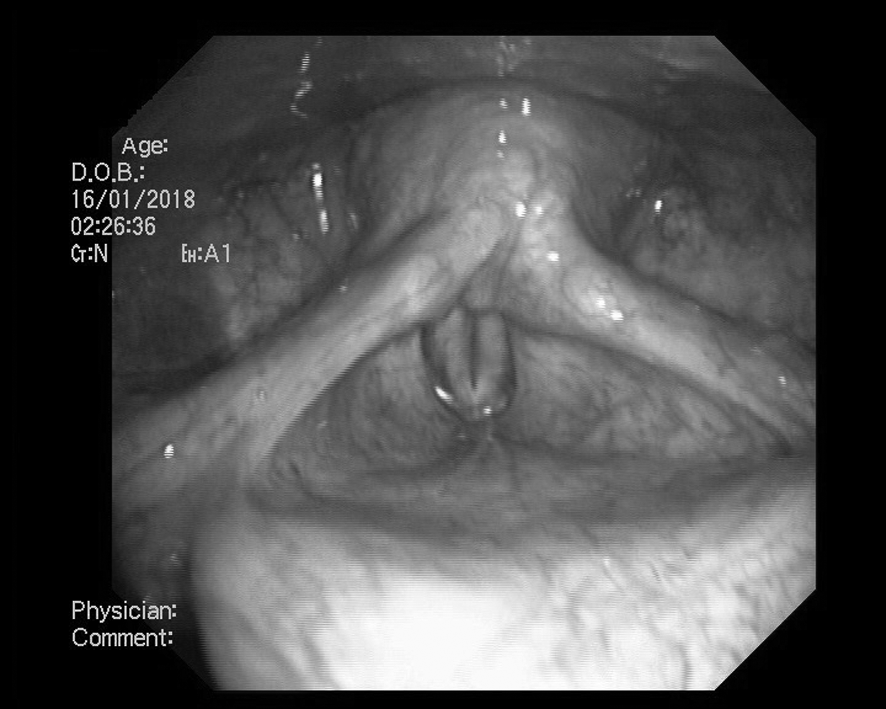

С 13.12.17 по 19.01.18 пациентке с диагнозом дисфония был проведен курс голосовой реабилитации в условиях стационара. После окончания лечения при эндоскопическом контроле отмечается розовая слизистая гортани. Голосовая щель симметрична, при фонации полностью смыкается за счет равномерного синхронного смыкания правой и левой голосовых складок (рис. 3). В настоящее время пациентка продолжает трудовую деятельность (учитель начальных классов), связанную с голосовой нагрузкой.

Рис. 3. После курса голосовой реабилитации. Полное смыкание голосовых складок при фонации.